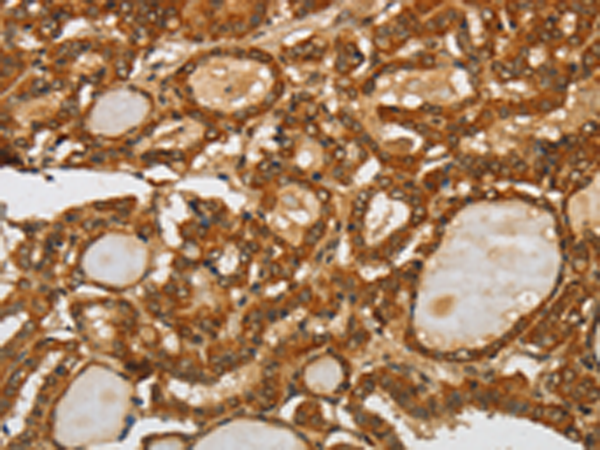

分类: 科研抗体货号: P08027别名: HNAC1; BCDase; LCDase; NCDase; N-CDase应用: WB,IHC反应种属: Human, Mouse, Rat